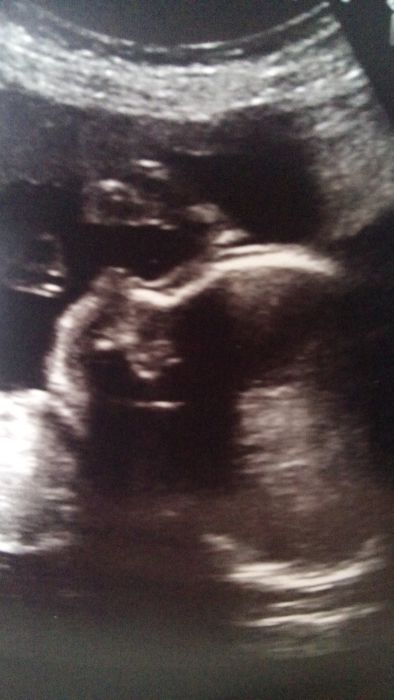

To je nas princ ze vcera.uz nejde udelat fotka celeho tela.

Ahojte holky.Adélko to bude zase dobrý usmiřování je nejlepší,zase bude dobře.Dupino krásná fotečka,já už se tak hrozně těším na zítra do poradny co nám dr poví jsem tak natěšená.Janičko tak už vám to určitě vypuklo to natáčení,Vlasti doufám že je ti dobře,zkus se na ten pás zeptat v lékarně tam jak prodávájí ty zdravotní pomůcky,punčochy na křečáky atd tam by to mnělo být.

Evi tam mě posílala na pro punčochu na ten křečák co na něj jím ty prásky ... zkusím to vidíš děkuju :) Adél držím palce :) a neboj to se uklidní a zas bude dobře jak říkáš všude je něco ...Dupi krásná fotka :)

taky me napadly nejaky ty zdravotnicky potreby a urcite Ti tam i poradi,Vlasti :-) Adel,nemas to ted lehky teda :-/,ale chlap dostane rozum a zas bude dobre. Dupi,to uz je teda obrik,kdyz se nevejde na fotku :-),ja uz bych tak chtela,aby byl ten mrnous s nami... :-) a pak budu jeste vzpominat,jak bylo fajn,kdyz byl v brisku ;-) :-D...

Dupi, parádní fotka ;) Adél, jsou to někdy roury ty chlapy :/ vždycky se sprajcnou, když jsou nejvíc potřeba. ... Berdi, budeš vzpomínat na kopání a hlazeni bříška. .. na to, ze je to sedm měsíců strachu (než uz může konečně bezpečně ven), ze nebudeš moci v noci spát kvůli panderu, ze kdekomu otikaji nohy a ruce, ze ti bude kopat třeba do žeber a do žaludku, a ze s tebou mlátí hormony jak s pubertakem... tak na to se taaak rychle zapomíná :D ja bych na jednu stranu chtěla mít dalších 15 týdnů za sebou (kouzelné 36+0 jako hranice donosenosti), ale zase mi utíká čas mojí princezny mezi prsty... teď si chce hrát s maminkou a vařit a vubec... je to takové fajn, přijdu si pak strašně nevdecna